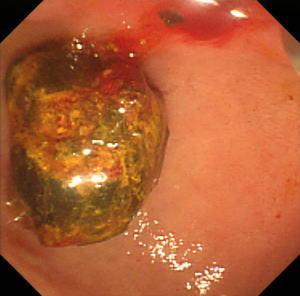

【EPLBD】 |

総胆管に15mm大の胆管結石を2個認めています(矢印)。 |

口径15~18mmの大口径拡張バルーンを用いて十二指腸乳頭(胆管の出口)の拡張術を実施しました。 |

矢印の間が拡張バルーンです。 |

乳頭拡張後に採石用のバスケット(金属線の器具)を用いて結石を破砕することなく除去しました。 |

除去した結石です。この方法では結石を破砕しなくて済むため、1回の処置でほぼすべての結石を除去することができます。 |